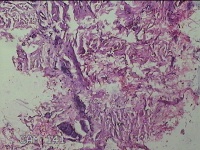

左手指结节

性别

男

年龄

42岁

临床诊断

皮下结节

一般病史

发现左手指结节2个月余。

标本名称

大体所见

灰白粉红色组织1x0.8x0.3cm一块,表面带梭形皮肤1x0.7cm,皮下见结节1x0.8cm,切开皮肤呈实性,切面灰白粉红色,质软。

图片无诊断价值。